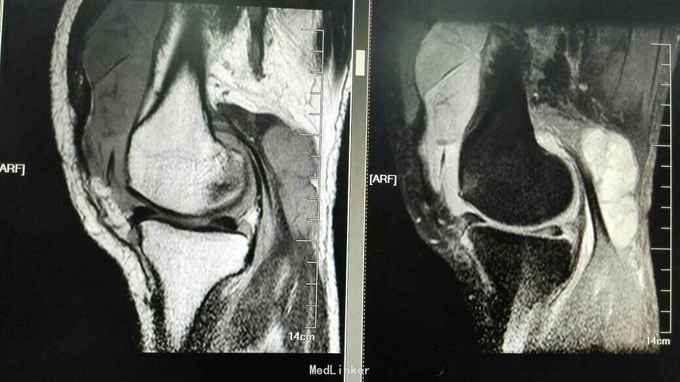

查体:右膝稍肿胀,皮温正常,右膝髌上囊处压痛(+),右膝屈曲稍受限(0~100度),余查体正常。 辅助检查:血常规、ESR、CRP正常 膝关节正侧位片:右膝关节退行性变,髌上囊肿胀 膝关节MRI提示:右膝髌上囊软组织占位,侵犯至股四头肌,考虑滑膜肉瘤可能性大 关节镜取活检提示滑膜肉瘤 全身PET-CT未见其它部位转移,肺无转移